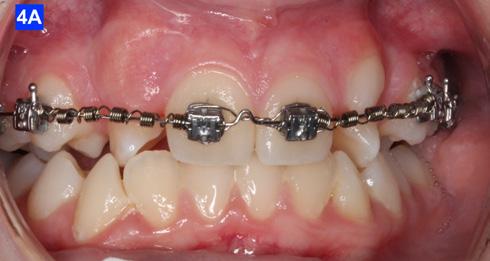

The maxillary cuspids were erupting mesially to the lateral incisors, with very little space to accommodate both teeth without an odontectomy. The expansion was continued (1/4 turn 2x per week), and an attempt was made to create more space for erupting cuspids with an open coil spring (OCS) – between the central incisors and the cuspids (Molar distalization spring, a .010 x .045 - Ortho Organizers). The OCS was measured and cut 4.0 mm longer than the available space. The maxillary arch wire was a .018 SS. An elastomeric chain (EC) was attached from the Hyrax to the lingual button on the lateral incisors. It was necessary to first pull the lateral incisors away from the alveolar process to prevent the break down of the buccal cortical bone around the cuspids (Figure

B, C).

4-A, Figure 3A: The patient transferred to our office, frontal view Figure 3B: The patient transferred to our office, maxilla, occlusal view Figure 3C: The patient transferred to our office, mandible, occlusal view Figure 4A: OCS, frontal view Figure 4B: Hyrax, occlusal view Figure 4C: Retraction of maxillary lateral incisors